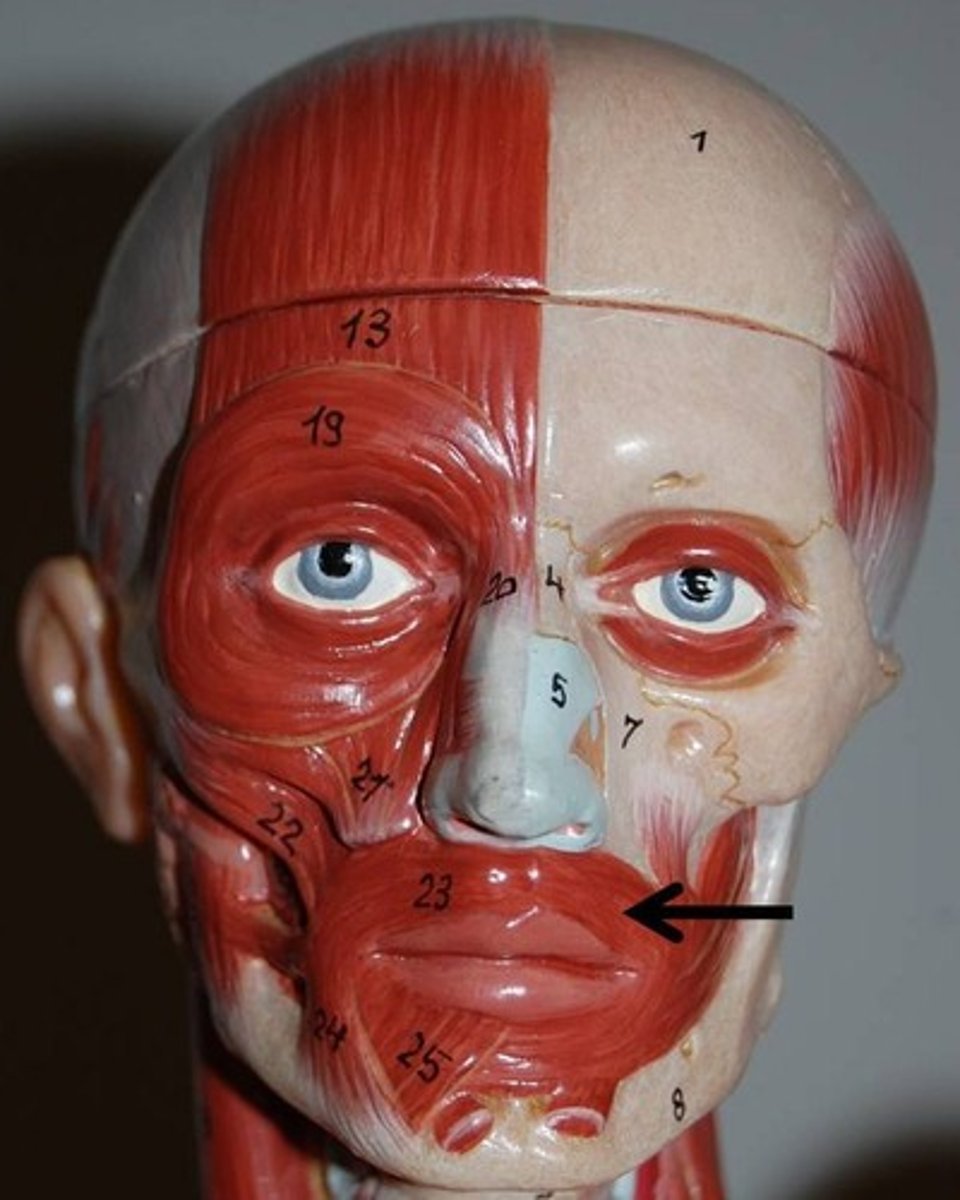

Orbicularis Oculi

Closes the eye

Orbicularis Oris

closes lips

Temporalis

Elevates and retracts mandible